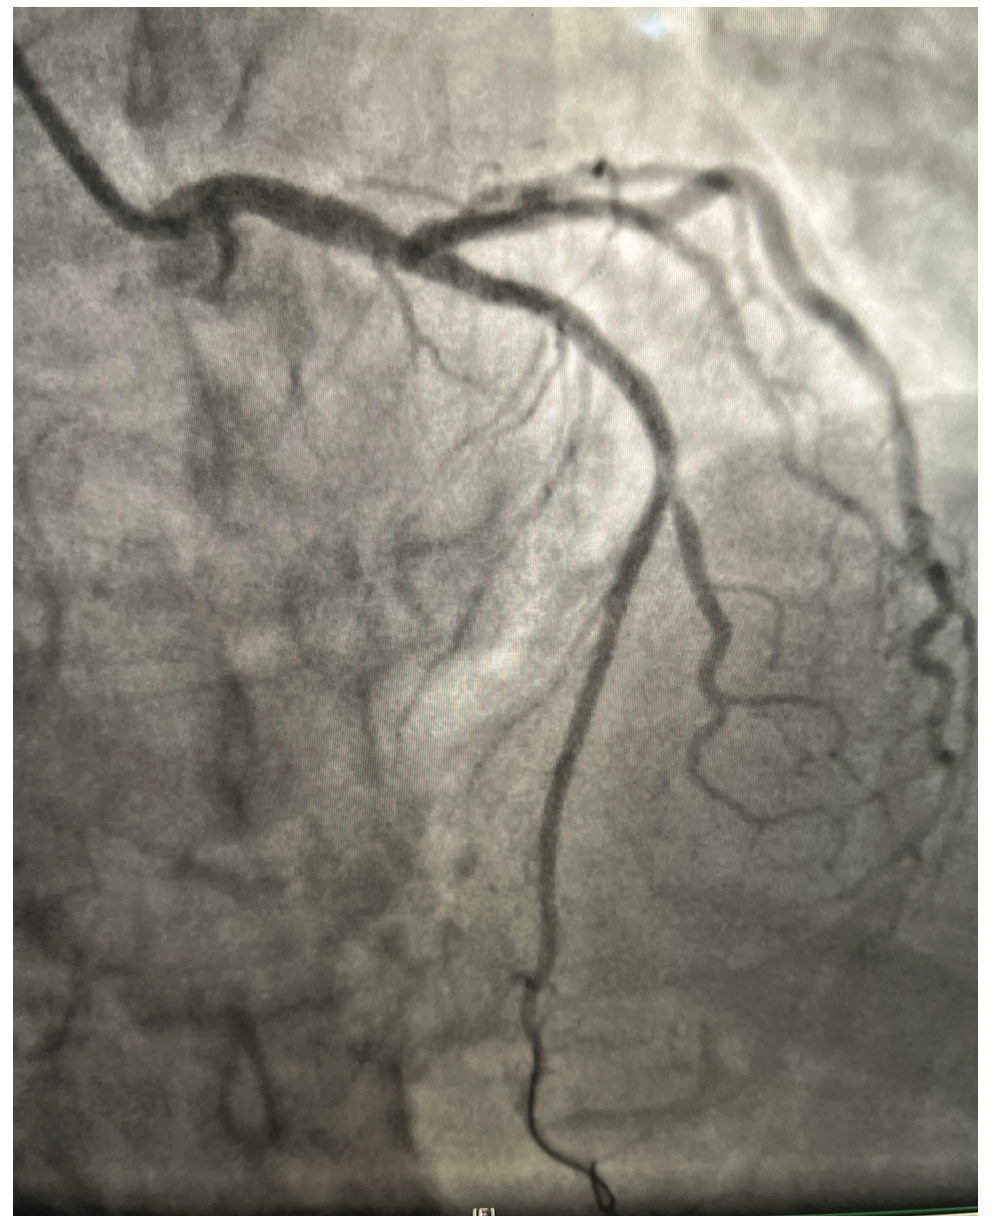

The left coronary artery was cannulated through the right radial artery with a 6 French Judkins left 3.5 guide catheter. The mid left anterior descending (LAD) artery showed a 70%-80% long lesion (Figure 1). After adequate anticoagulation with heparin, an .14-inch Runthrough wire (Terumo) was used to wire the LAD without difficulty. The patient’s vitals were within normal range. An uneventful predilatation of the mid LAD lesion with a compliant 2.5 mm x 20 mm balloon was performed. After predilatation, an angiogram showed no angiographic dissection and TIMI-III flow (Figure 2). A 2.75 mm x 38 mm drug-eluting stent was advanced to the lesion without any difficulty. The stent was positioned with a contrast puff and direct fluoroscopy. Just prior to the stent placement, the patient’s rhythm became ventricular fibrillation. The rhythm was immediately identified and a nurse began looking for defibrillator pads. Another cath lab technologist moved to the sterile drape to start cardiopulmonary resuscitation (CPR), with an adjustment of the cath lab table and fluoroscopy camera on the way. Defibrillator pads were found, and placed on the patient’s chest and side. An external shock was delivered and the patient converted to normal rhythm. Less than 30 seconds of CPR was performed. Since we were certain of the position of the stent, and no angiographically significant dissection or perforation was visualized, we deployed the stent in the mid LAD during the chaos of getting defibrillator pads and preparation for CPR. The patient remained in ventricular fibrillation even after stent deployment. Regular rhythm was restored only after an external shock and the patient immediately regained complete consciousness. Multiple coronary images were obtained, but no abnormal coronary etiology of the ventricular fibrillation could be found (Figure 3). Post dilatation of the stent was performed with a 3.0 mm noncompliant balloon. A final angiogram showed good stent apposition without any complications. A limited cardiac cath lab echocardiogram showed no evidence of pericardial effusion. The procedure was concluded successfully without any final complications.